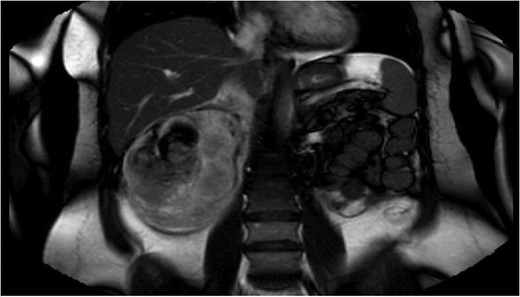

Fluid resuscitation and IV antibiotics were commenced, and an abdominal ultrasound performed. It revealed the presence of a large heterogenous right renal mass. Further evaluation was performed with magnetic resonance cholangiopancreatography. Findings were of a 5.7 × 4.6 cm2 exophytic mass of high T1 signal intensity arising from the posterior right kidney. Adjacent to the mass was a large 8.3 × 10 cm2 retroperitoneal haematoma (Fig. 1). These findings were consistent with a ruptured angiomyolipoma. The adjacent common bile duct was dilated at 8 mm, secondary to mass effect (Fig. 2).

Magnetic resonance cholangiopancreatography (MRCP) on admission, showing an exophytic mass arising from posterior right kidney, with adjacent 8.3 × 10 cm2 retroperitoneal haematoma.